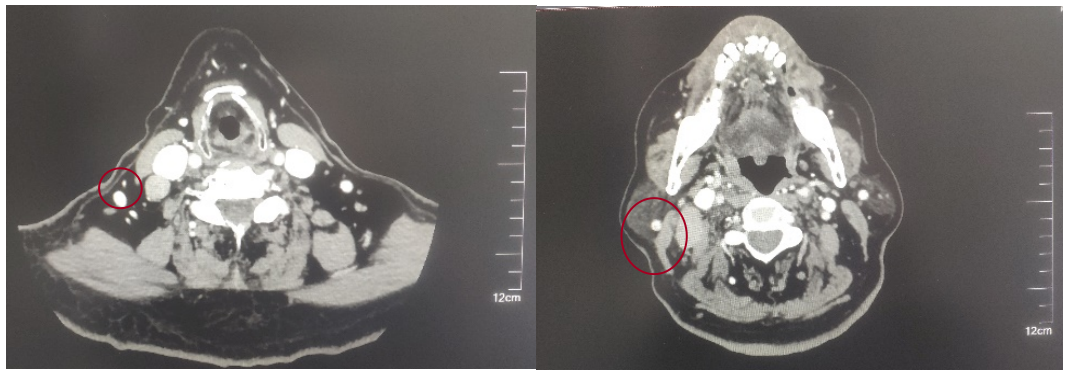

2022-05-05鼻咽部增强CT示:鼻咽CA并左侧翼腭弓、海绵窦受侵,伴邻近蝶窦、左侧筛窦、枕骨斜坡、左侧框下裂骨质破坏;右侧颈部多发肿大淋巴结(最大2.4×1.4cm),考虑转移;2.双侧梨状窝闭塞。

后患者至江苏省肿瘤医院放疗科就诊,2022-06-06完善头颅MR检查:

修正诊断:鼻咽癌T3N1M0,Ⅲ期。